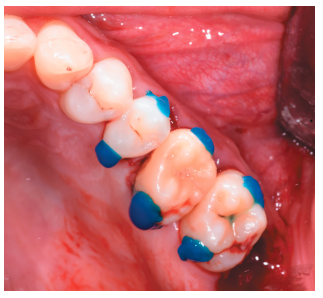

La fluorosis dental es una condición irreversible originada durante el desarrollo dental que genera pigmentaciones intrínsecas, alteraciones en el esmalte manifestadas a manera de manchas blancas, amarillas o marrones, que perjudican la estética y repercuten en el desenvolvimiento social. El presente reporte de caso clínico describe la combinación de los procedimientos de microabrasión y blanqueamiento dental, como alternativas en la eliminación de pigmentaciones dentales. Después del diagnóstico de la patología, verificación de ausencia de lesiones pulpares y caries, una explicación minuciosa a la paciente y obtención del consentimiento informado, se realizó limpieza de las superficies dentales y, bajo aislamiento absoluto, se procedió a realizar la técnica de microabrasión mediante ácido clorhídrico al 6,6% siguiendo las instrucciones del fabricante. Concluido el procedimiento y, observando que era posible mejorar aún más la estética, se decidió ejecutar el procedimiento de blanqueamiento dental, a base de peróxido de hidrógeno al 40% en el consultorio, seguido por peróxido de carbamida al 10% aplicado en el domicilio. Al finalizar el tratamiento se observó uniformidad en el color dental, conjugados con una evidente mejora en la calidad de vida y relación social de la paciente.